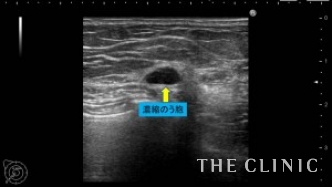

この方は、10年前に脂肪注入を受けられていて、近年の乳がん検診にてしこりを指摘されたとのこと。指摘後は何もせず放置していたが、昨年ぐらいから自分でもしこりを感じるようになったため、当院を受診されました。

しこりの大きさは3mmから7mmと非常に小さなしこりでしたが、ご本人が治療を希望されたためエコー下に穿刺吸引しました。右のしこりの1つは乳腺内の腫瘤でしたが濃縮のう胞でした。

吸引した脂肪です。両側合わせて12個のオイルシストを穿刺吸引しました。